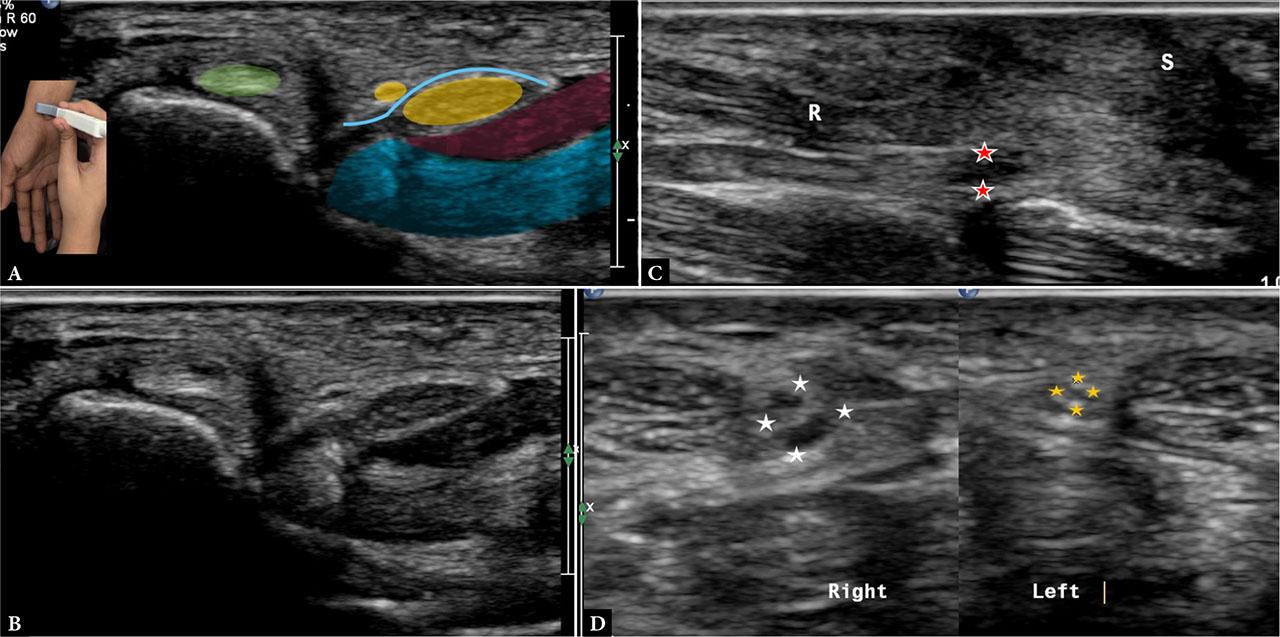

Sonographic identification of the palmar cutaneous branch of the median nerve (PCBmn) is both feasible and clinically valuable. In one study using 17–5 MHz probes, the PCBmn was visualized from its origin to slightly distal to the wrist crease in 83% of healthy volunteers; in symptomatic individuals, abnormalities such as focal swelling, neuroma, or transection were detected in 55% of cases. Another sonographic study detailed its course: it emerges radially from the median nerve, pierces the antebrachial fascia between the flexor carpi radialis and palmaris longus tendons, and then travels superficial to the abductor pollicis brevis muscle (Fig. 7).

Images A and B demonstrate one of the variant anatomical courses of the palmar cutaneous branch of the median nerve (PCBmn) (small yellow circle). Here, the nerve can be seen ulnar to the flexor carpi radialis (green circle) and superficial to the flexor retinaculum (blue) at the level of the carpal tunnel. In this patient, the nerve courses in the subcutaneous plane more distally than usual. Note the probe position in the inset. The median nerve (yellow circle), flexor tendons (blue), and an incidental low-lying muscle belly of flexor tendons (red) can also be seen. Image C shows an end-neuroma (asterisk) in the PCBmn in a patient with a penetrating injury in the distal forearm. The flexor carpi radialis (R) lies superficial to the nerve, and overlying hypoechoic scar (S) is also present. Image D demonstrates focal thickening of the PCBmn (white asterisk) as it courses medial to the flexor carpi radialis tendon in a patient with thenar pain. This can be compared with the contralateral normal side (yellow asterisk). The median nerve was normal in course and caliber in this patient

Extensive anatomical variation exists in the PCBmn, with the nerve piercing the antebrachial fascia at variable distances from the wrist crease, sometimes coursing through the carpal tunnel, travelling within the sheath or even within the substance of the flexor carpi radialis tendon; less commonly, it is associated with the palmaris longus. Awareness of these variants is essential to avoid iatrogenic injury during carpal tunnel release and to guide postoperative evaluation of persistent pain, which usually presents as ‘pillar pain’(14,15,16).